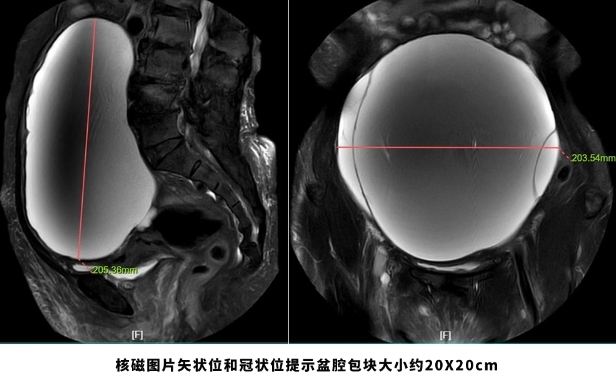

百度网页版:69岁老妇挺着“大肚子”来医院,检查后竟“怀”了个巨大肿瘤!